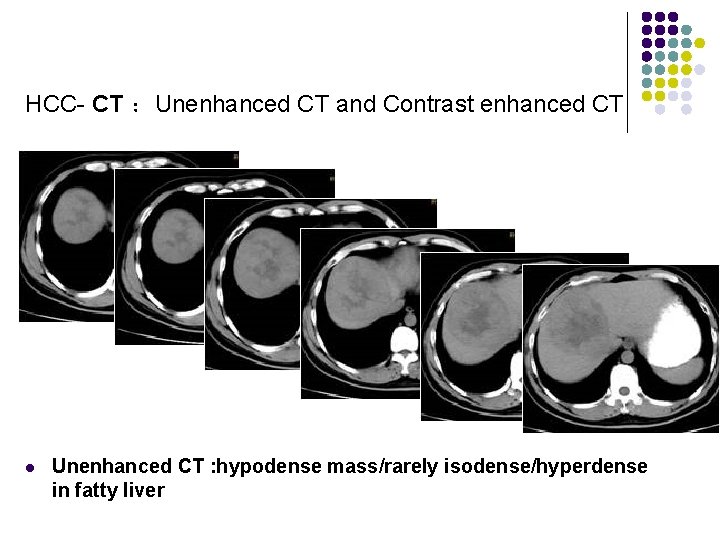

HCC- CT l l sensitivity of 63% in cirrhosis, 80% without cirrhosis) hypodense mass/rarely isodense/hyperdense in fatty liver: l dominant mass with satellite nodules l mosaic pattern = multiple nodular areas with differing attenuation on CECT (up to 63%) l diffusely infiltrating neoplasm encapsulated HCC = circular zone of radiolucency surrounding the mass (12 -67%) False-positive: confluent fibrosis, regenerative nodule

HCC- CT :Unenhanced CT and Contrast enhanced CT l Unenhanced CT : hypodense mass/rarely isodense/hyperdense in fatty liver